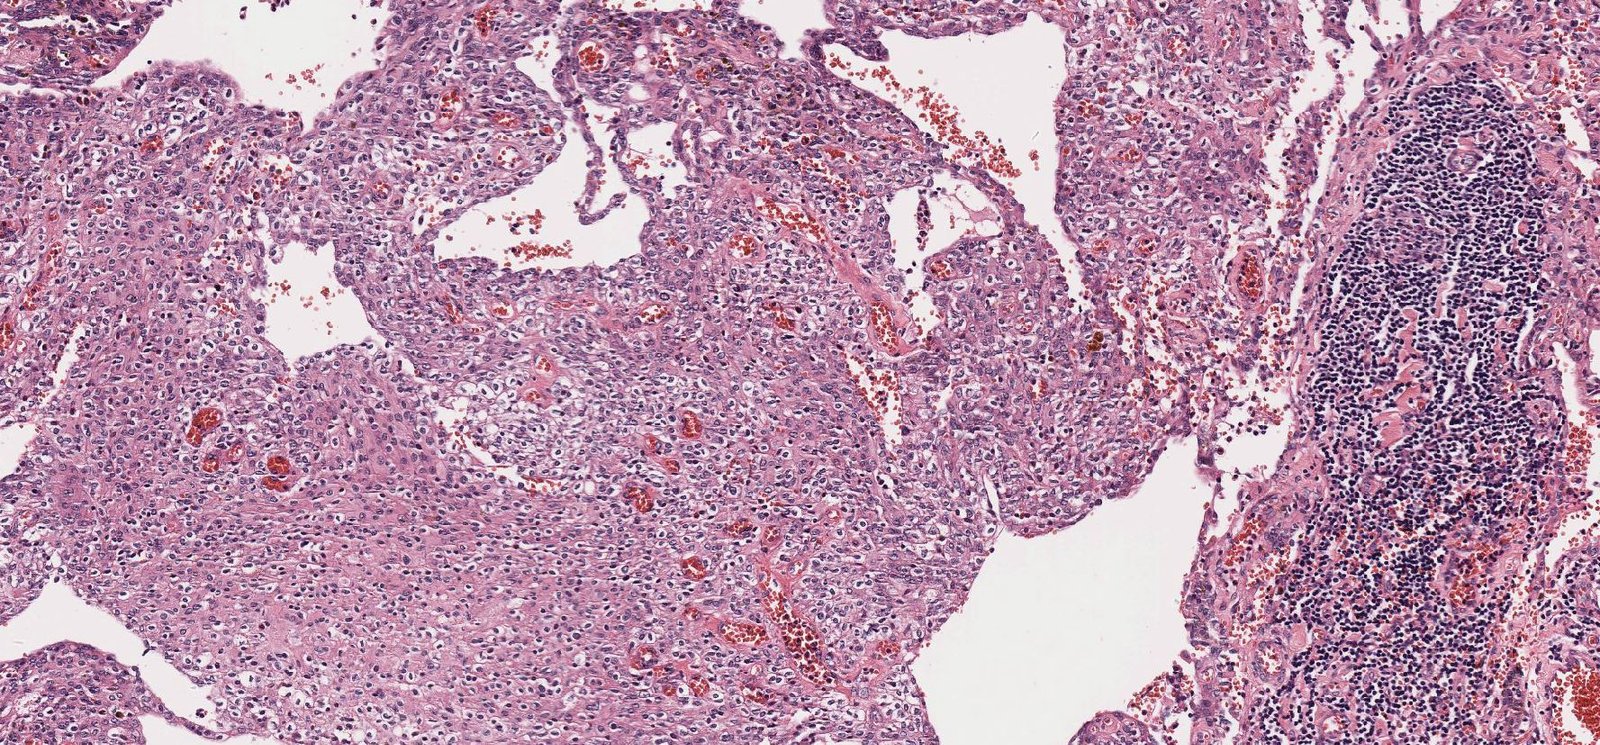

Case: NeckMass